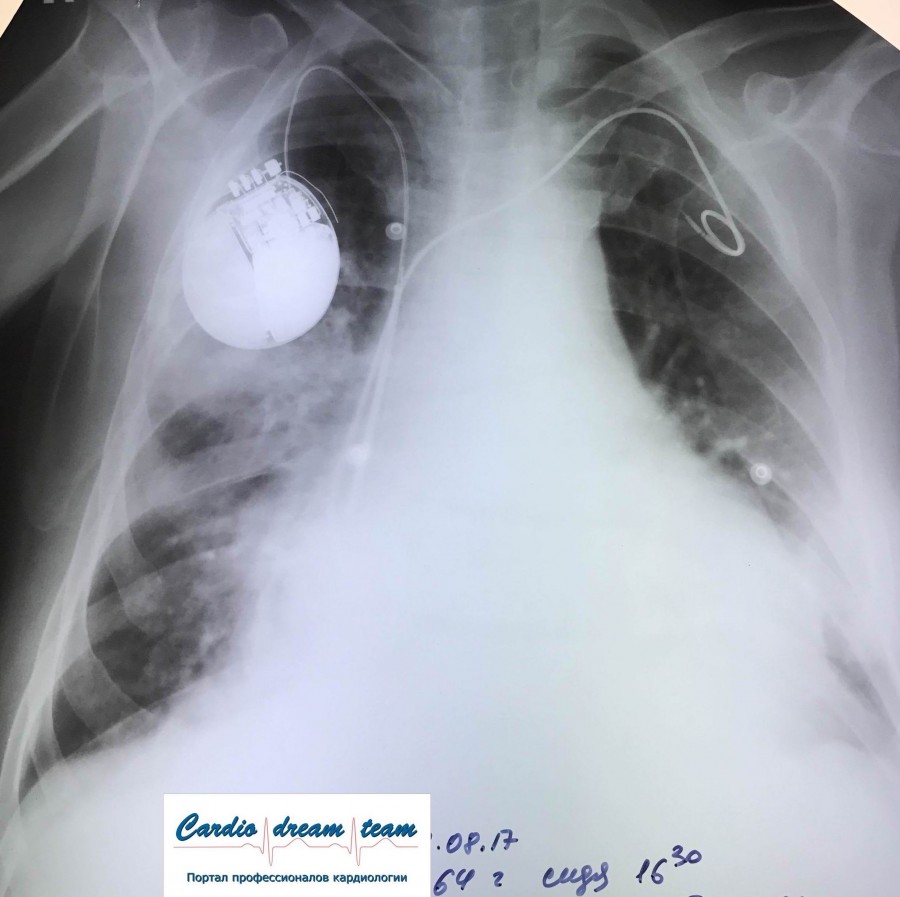

Гидроторакс. Серия снимков.

1 - лежа. Так делать не надо! Надо только сидя!

2 - сидя. Понятно, что гидроторакс за раз не победить

3 - удалено 1100.

4 - удалено ещё 1200. И диуретики все эти дни.